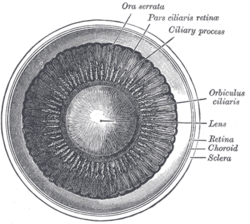

Schematic diagram of the human eye. | |

Structure

The lens has three main parts: the lens capsule, the lens epithelium, and the lens fibers. The lens capsule forms the outermost layer of the lens and the lens fibers form the bulk of the interior of the lens. The cells of the lens epithelium, located between the lens capsule and the outermost layer of lens fibers, are found only on the anterior side of the lens. The lens itself lacks nerves, blood vessels, or connective tissue.[4]